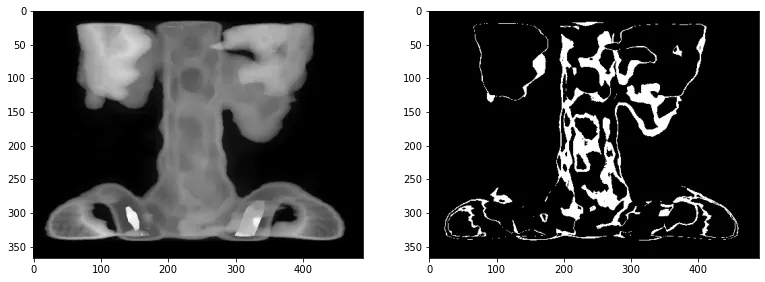

plt.figure(117, figsize=[13,5])

plt.subplot(1,2,1)

im_spine = cv2.imread('spine.tif', cv2.IMREAD_GRAYSCALE)

plt.imshow(im_spine, cmap='gray')

ret, threshold = auto_thresholding(im_spine, return_threshold=True)

print("Thresholding with Otsu's method:", threshold)

plt.subplot(1,2,2)

plt.imshow(ret, cmap='gray')

Python

복사

Thresholding with Otsu's method: 64

Plain Text